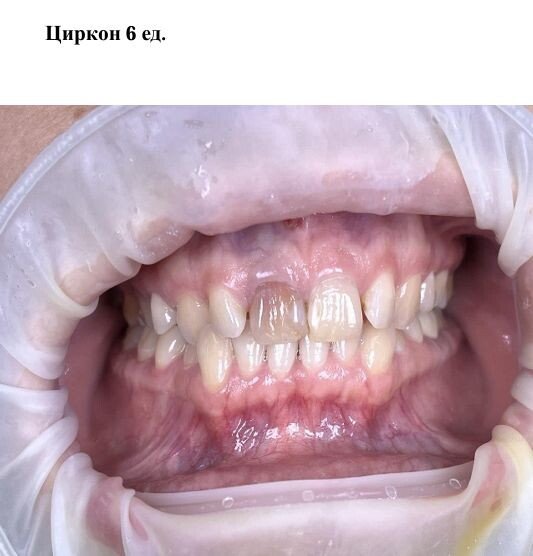

Фотогалерея